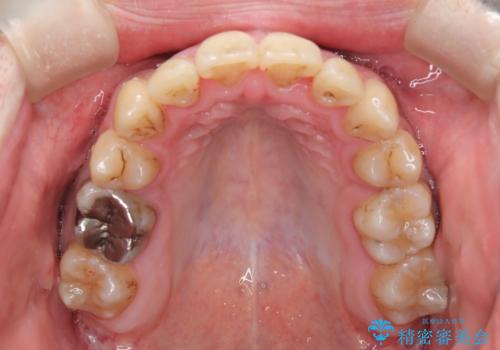

患者様にはかなり満足していただける結果となりました。

八重歯(3番)などは歯肉移植も検討できればよいかなと思います。

骨格的に上顎骨が小さいために相対的に下顎骨が前に出ていたため、歯の傾きなど理想的な仕上がりが難しく、外科矯正ではなく歯列矯正の場合はカモフラージュ矯正になること説明の上、矯正治療を進めることになりました。

上顎は左右5番抜歯、下顎は左右4番抜歯しています。